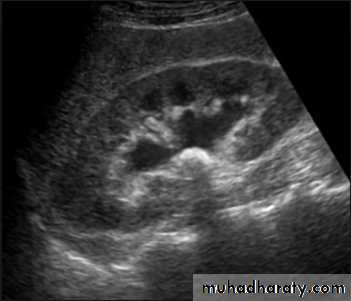

Ultrasonic descriptive terms

Typically, a cyst containing a clear fluid has few if any echoes (anechoic =black ) ,

Tissues such as liver and spleen give a picture with rather homogeneous small echoes due to the fibrous interstitial tissue (hypo echoic , isoechoic or hyper echoic = gray scale spectrum ) ,

Metals or Calcium in the bone and stones ( echogenic = white ) .

Ultrasound is typically ordered to exclude , stones , hydronephrosis or to evaluate renal size or suspected renal cysts .